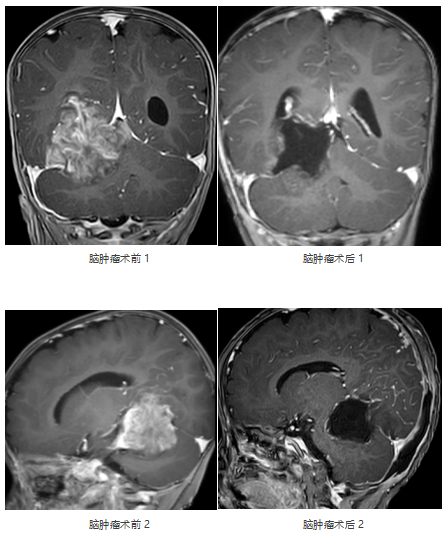

入院后,患儿头颅MRI平扫+增强提示:右侧小脑幕上下骑跨巨大肿瘤,压迫右侧丘脑、侧脑室、脑干、小脑等重要结构,考虑胚胎型肿瘤可能性大。肿瘤与周围组织无明显边界,手术难度极大、风险极高。

2026年3月3日,由张玉琪院长主刀,经枕下幕上入路小脑幕上、下病变切除术。手术历时4小时,镜下近全切除肿瘤,周围脑干、颅神经及血管保护良好,出血仅100ml。术后患儿转入NICU(新生儿重症监护病房),次日平稳返回普通病房。病理确诊为胚胎性肿瘤,WHO Ⅳ级(世界卫生组织(WHO)根据肿瘤恶性程度划分的最高级别(IV级)的恶性肿瘤)。术后虽康复情况充满挑战,但由医护团队通过中西医结合治疗后顺利恢复健康,并于术后第17天顺利启动第一周期化疗。